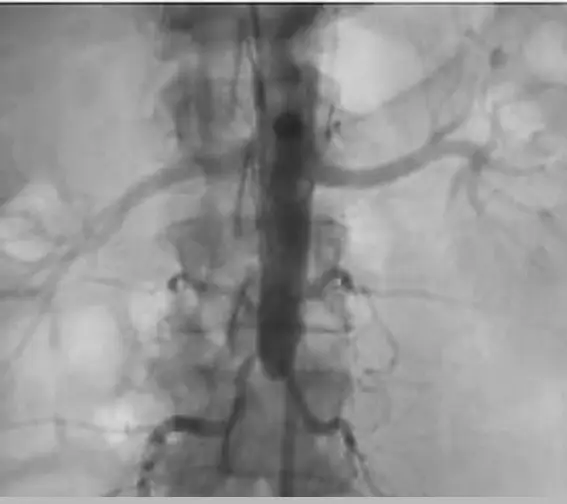

本題提供的是一張腹部主動脈的數位減影血管攝影(DSA)影像。

- 導管途徑:從影像可見導管由上方往下延伸,對應題目所述的「從肱動脈(brachial artery)穿刺」的順行性(antegrade)攝影。

- 正常顯影區域:顯影劑清楚填滿了近端的腹主動脈(abdominal aorta),並且可見雙側腎動脈(renal arteries)正常顯影,血流順利灌注至雙側腎臟實質。

- 異常影像特徵:在雙側腎動脈分支出來下方的水平(腎下主動脈,infrarenal aorta),主動脈的顯影劑呈現「突然截斷(abrupt cutoff)」的現象,完全沒有對比劑向下流入遠端的主動脈、主動脈分叉處(aortic bifurcation)及雙側總髂動脈(common iliac arteries)。

- 側支循環:在阻塞處周圍隱約可見細微的側支循環(collateral vessels)試圖向下肢供血,這是慢性動脈粥狀硬化阻塞常見的代償現象。

綜合臨床病史與影像特徵,病人出現「股動脈穿刺失敗」,在臨床上強烈暗示下肢動脈或主動脈末端存在嚴重的狹窄或阻塞。改以肱動脈進行順行性血管攝影後,影像證實了顯影劑在腎下主動脈處完全中斷,無法向下灌注至髂動脈。這個影像發現是典型的「遠端主動脈阻塞(Distal aortic occlusion)」,在臨床上若合併雙側髂動脈阻塞,即為著名的 Leriche syndrome。因此,(A) 為唯一且最精確的診斷。

- 影像特徵:血管攝影上呈現腎動脈下方的腹主動脈顯影劑平齊截斷,並伴隨豐富的腰動脈、下腸繫膜動脈等側支循環(collaterals)。